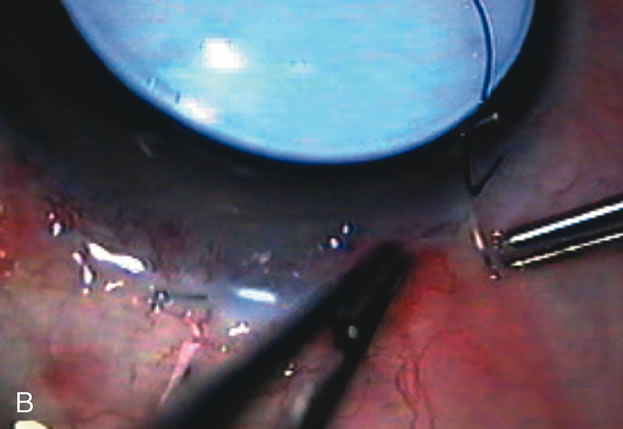

Fig. 2. Wound modulation and revision. A. MMC decreases the likelihood of bleb failure in high-risk eyes undergoing combined cataract and glaucoma surgery. Overusage of this potent cytotoxic drug should be avoided owing to a myriad of problems related to the formation of an avascular bleb. B. Office-based laser revision of the operative wound allows for increased postoperative flexibility with less complications. The correct number and tension of scleral flap sutures allows the surgeon to strive for a safe immediate postoperative IOP range. When fibrosis occurs at approximately 1 week, suturelysis or release of sutures increases filtration while avoiding unwanted hypotony.